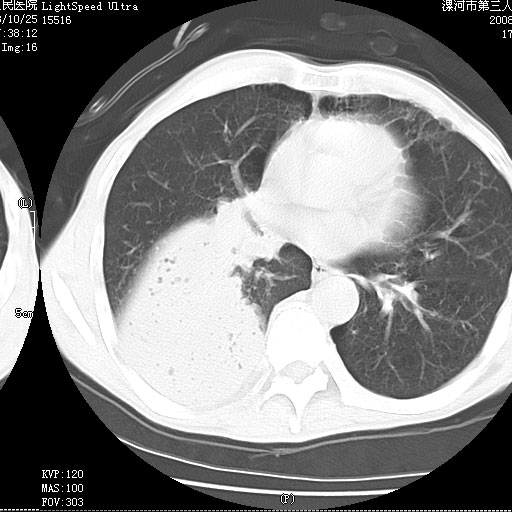

病灶边缘清---多个含气小腔---近端未见通畅气管影-----支持-----慢性肺脓肿继发阻塞性肺不张

阻塞性肺不张原因-----脓液未排出

病变按肺叶分布,病变内可见多个小空腔影,未见充气支气管影,中间段支气管管腔肺窗示密度欠均匀,下肺支气管分叉处基底段支气管隐约可见,未见明显狭窄,中叶支气管通畅,

考虑:阻塞性肺炎伴小脓肿形成可能性大。(痰栓可能性大)

阻塞性肺炎,肺脓肿形成。依据,右下支气管不通,大片实变形内可见小气泡。不支持肺不张。

右下肺阻塞性炎症,内见多发气体影,以肺叶分布.不支持不张.

右肺下叶肺脓肿,右肺下叶支气管痰栓形成。